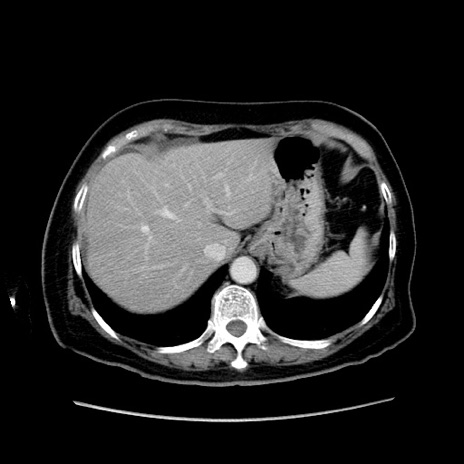

症例19(横断像)

【症例】80歳代女性

【主訴】下腹部痛

【現病歴】約8時間前より下腹部痛の出現あり、救急外来受診。

【既往歴】両側付属器切除

【身体所見】意識清明、下腹部正中に手術痕あり、その部位に一致して圧痛と反跳痛あり。腸蠕動音は亢進。

【データ】WBC 9300、CRP 0.15